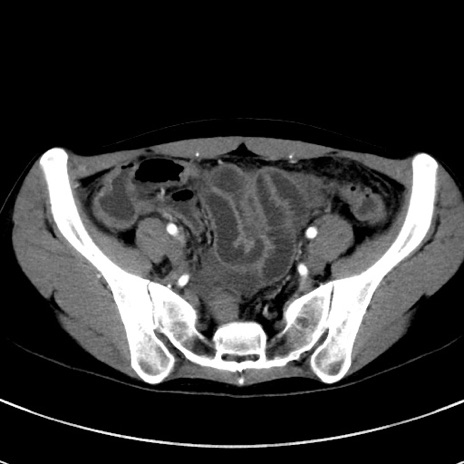

症例17(横断像)

【症例】20歳代女性

【主訴】嘔吐、下腹部痛

【現病歴】昨日夕食後に嘔吐し下腹部痛が出現。本日になっても嘔吐持続し改善しないため来院。

【身体所見】意識清明、BT 37.2℃、BP 108/67mmHg、腹部:平坦、やや硬、下腹部正中から右にかけて圧痛あり、反跳痛軽度あり、tapping pain(+)。

【データ】WBC 13600、CRP 14.94